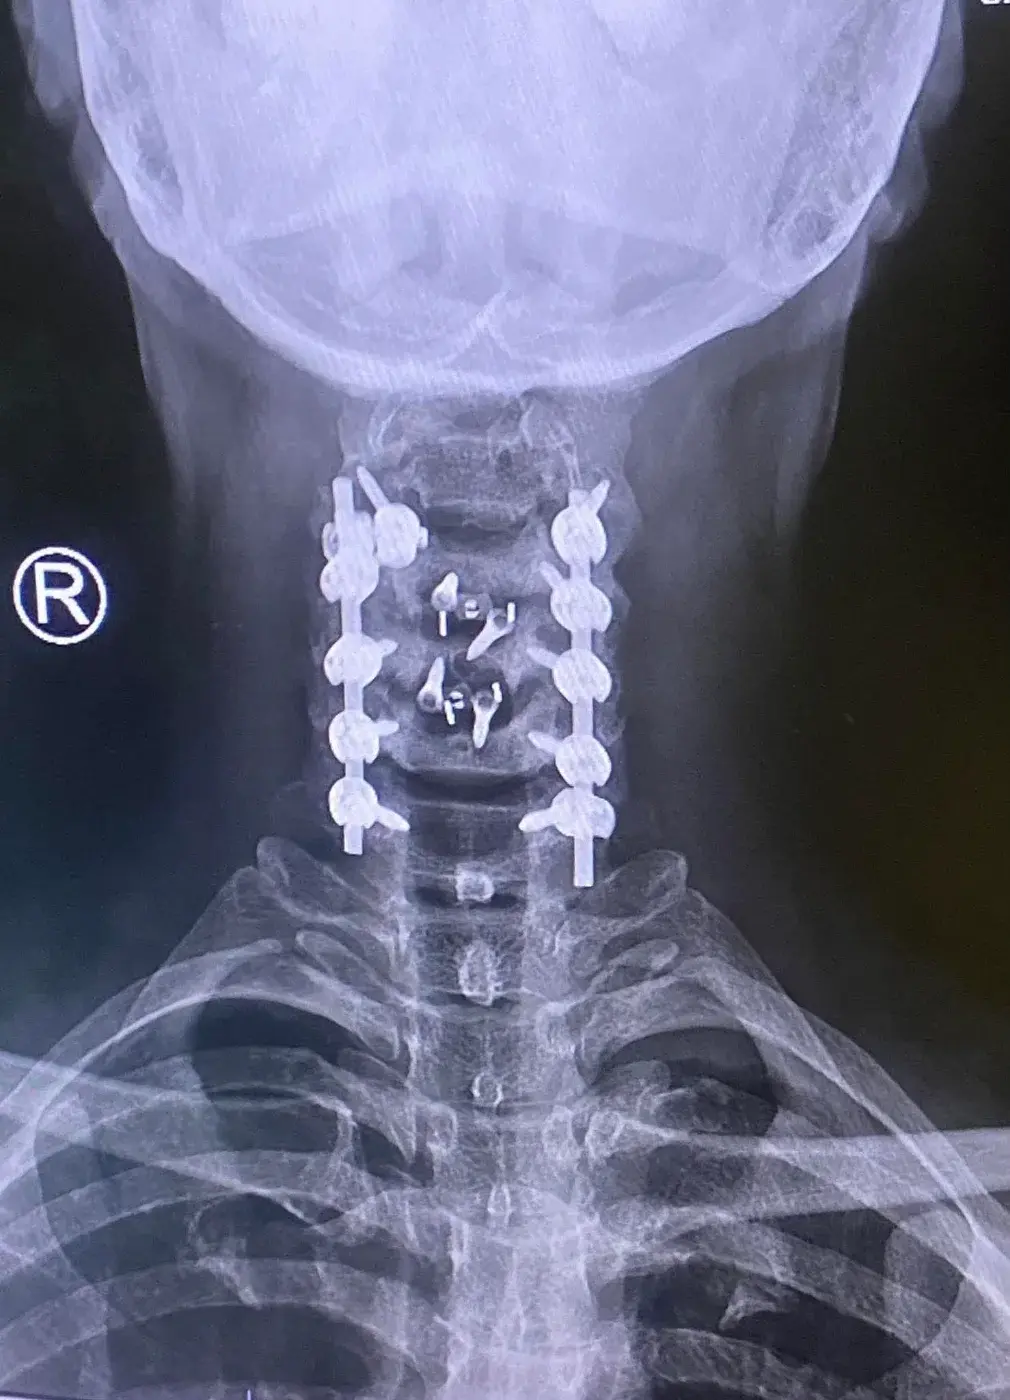

โทนเล่าว่า ก่อนหน้านี้เขาเคยเชื่อว่า ตัวเองสุขภาพแข็งแรง ไม่จำเป็นต้องซื้อประกัน เพราะยังหนุ่มแน่น ไม่ป่วยง่าย และหากป่วยจริง ๆ ก็ยังมี บัตรทอง 30 บาทรักษาทุกโรค อยู่แล้ว แต่ความคิดทั้งหมดเปลี่ยนไป เมื่อวันหนึ่งเขาตรวจพบว่าเป็น “โรคหมอนรองกระดูกที่คอเคลื่อนกดทับเส้นประสาท” ซึ่งมักเกิดในผู้สูงอายุ แต่กลับเกิดขึ้นกับเขาในวัยยังไม่ถึงกลางคน

โรคนี้ทำให้เขาต้องเข้ารับการ ผ่าตัดถึง 3 ครั้ง รวมค่าใช้จ่ายกว่า 3 ล้านบาท

รอบที่ 1: ผ่าตัดครั้งแรก ค่ารักษาเกิน 1 ล้านบาท

รอบที่ 2: อาการยังไม่ดีขึ้น ต้องผ่าซ้ำอีกครั้ง

รอบที่ 3: ผ่าตัดใหญ่ครั้งสุดท้ายที่โรงพยาบาลศิริราช ปิยมหาราชการุณย์ ใช้เวลาผ่าตัดกว่า 6 ชั่วโมง และต้องพัก ICU อีก 2 วัน